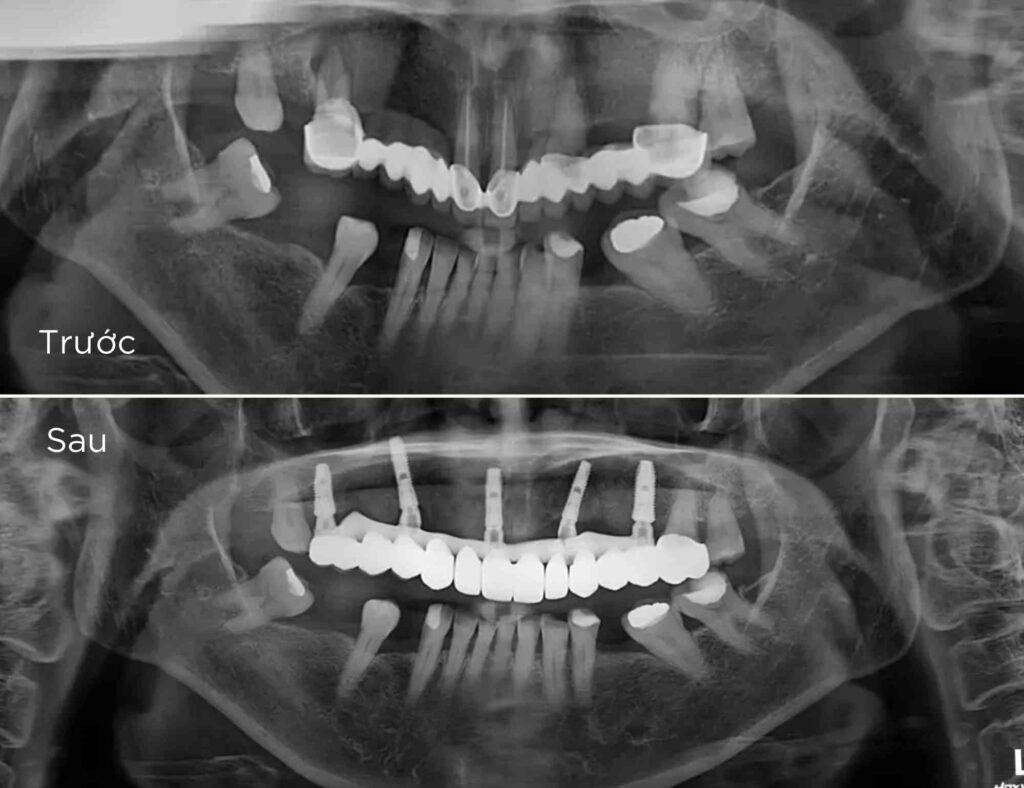

- 1. Khám và tư vấn: Bác sĩ sẽ khám và tư vấn chi tiết về tình trạng răng miệng của bạn, đánh giá liệu bạn có phù hợp để cấy ghép implant hay không.Chụp X-quang và lập kế hoạch điều trị: Chụp X-quang để xác định cấu trúc xương hàm, từ đó lập kế hoạch cấy ghép chi tiết.

- 2. Chụp X-quang và lập kế hoạch điều trị: Chụp X-quang để xác định cấu trúc xương hàm, từ đó lập kế hoạch cấy ghép chi tiết.

- 4. Lên kế hoạch và thiết kế máng hướng dẫn cắm implant 3D: Tại nha khoa Ken bạn có thể an tâm là implant sẽ được đặt ở vị trí đúng theo 3 chiều không gian - để có thể chịu lực ăn nhai tối ưu như răng thật. Các trụ implant sẽ được đặt vào trong xương qua máng hướng dẫn phẫu thuật được thiết kế trong phần mềm kỹ thuật số đảm bảo an toàn và độ chính xác cao.

- 5. Phẫu thuật đặt implant: Đặt các trụ implant vào xương qua máng hướng dẫn phẫu thuật kỹ thuật số và được tiến hành bởi bác sĩ chuyên khoa.

- 6. Phục hình tạm trên implant toàn hàm ALL-ON-X: Trong các trường hợp bệnh nhân mất răng toàn hàm phục hình tạm được gắn cho bệnh nhân ngay sau khi phẫu thuật.

- 8. Phục hình sứ trên implant toàn hàm ALL-ON-X: Sau khi các trụ implant đã tích hợp trong xương hàm, phục hình tạm trước đó sẽ được thay thế bời phục hình sứ.